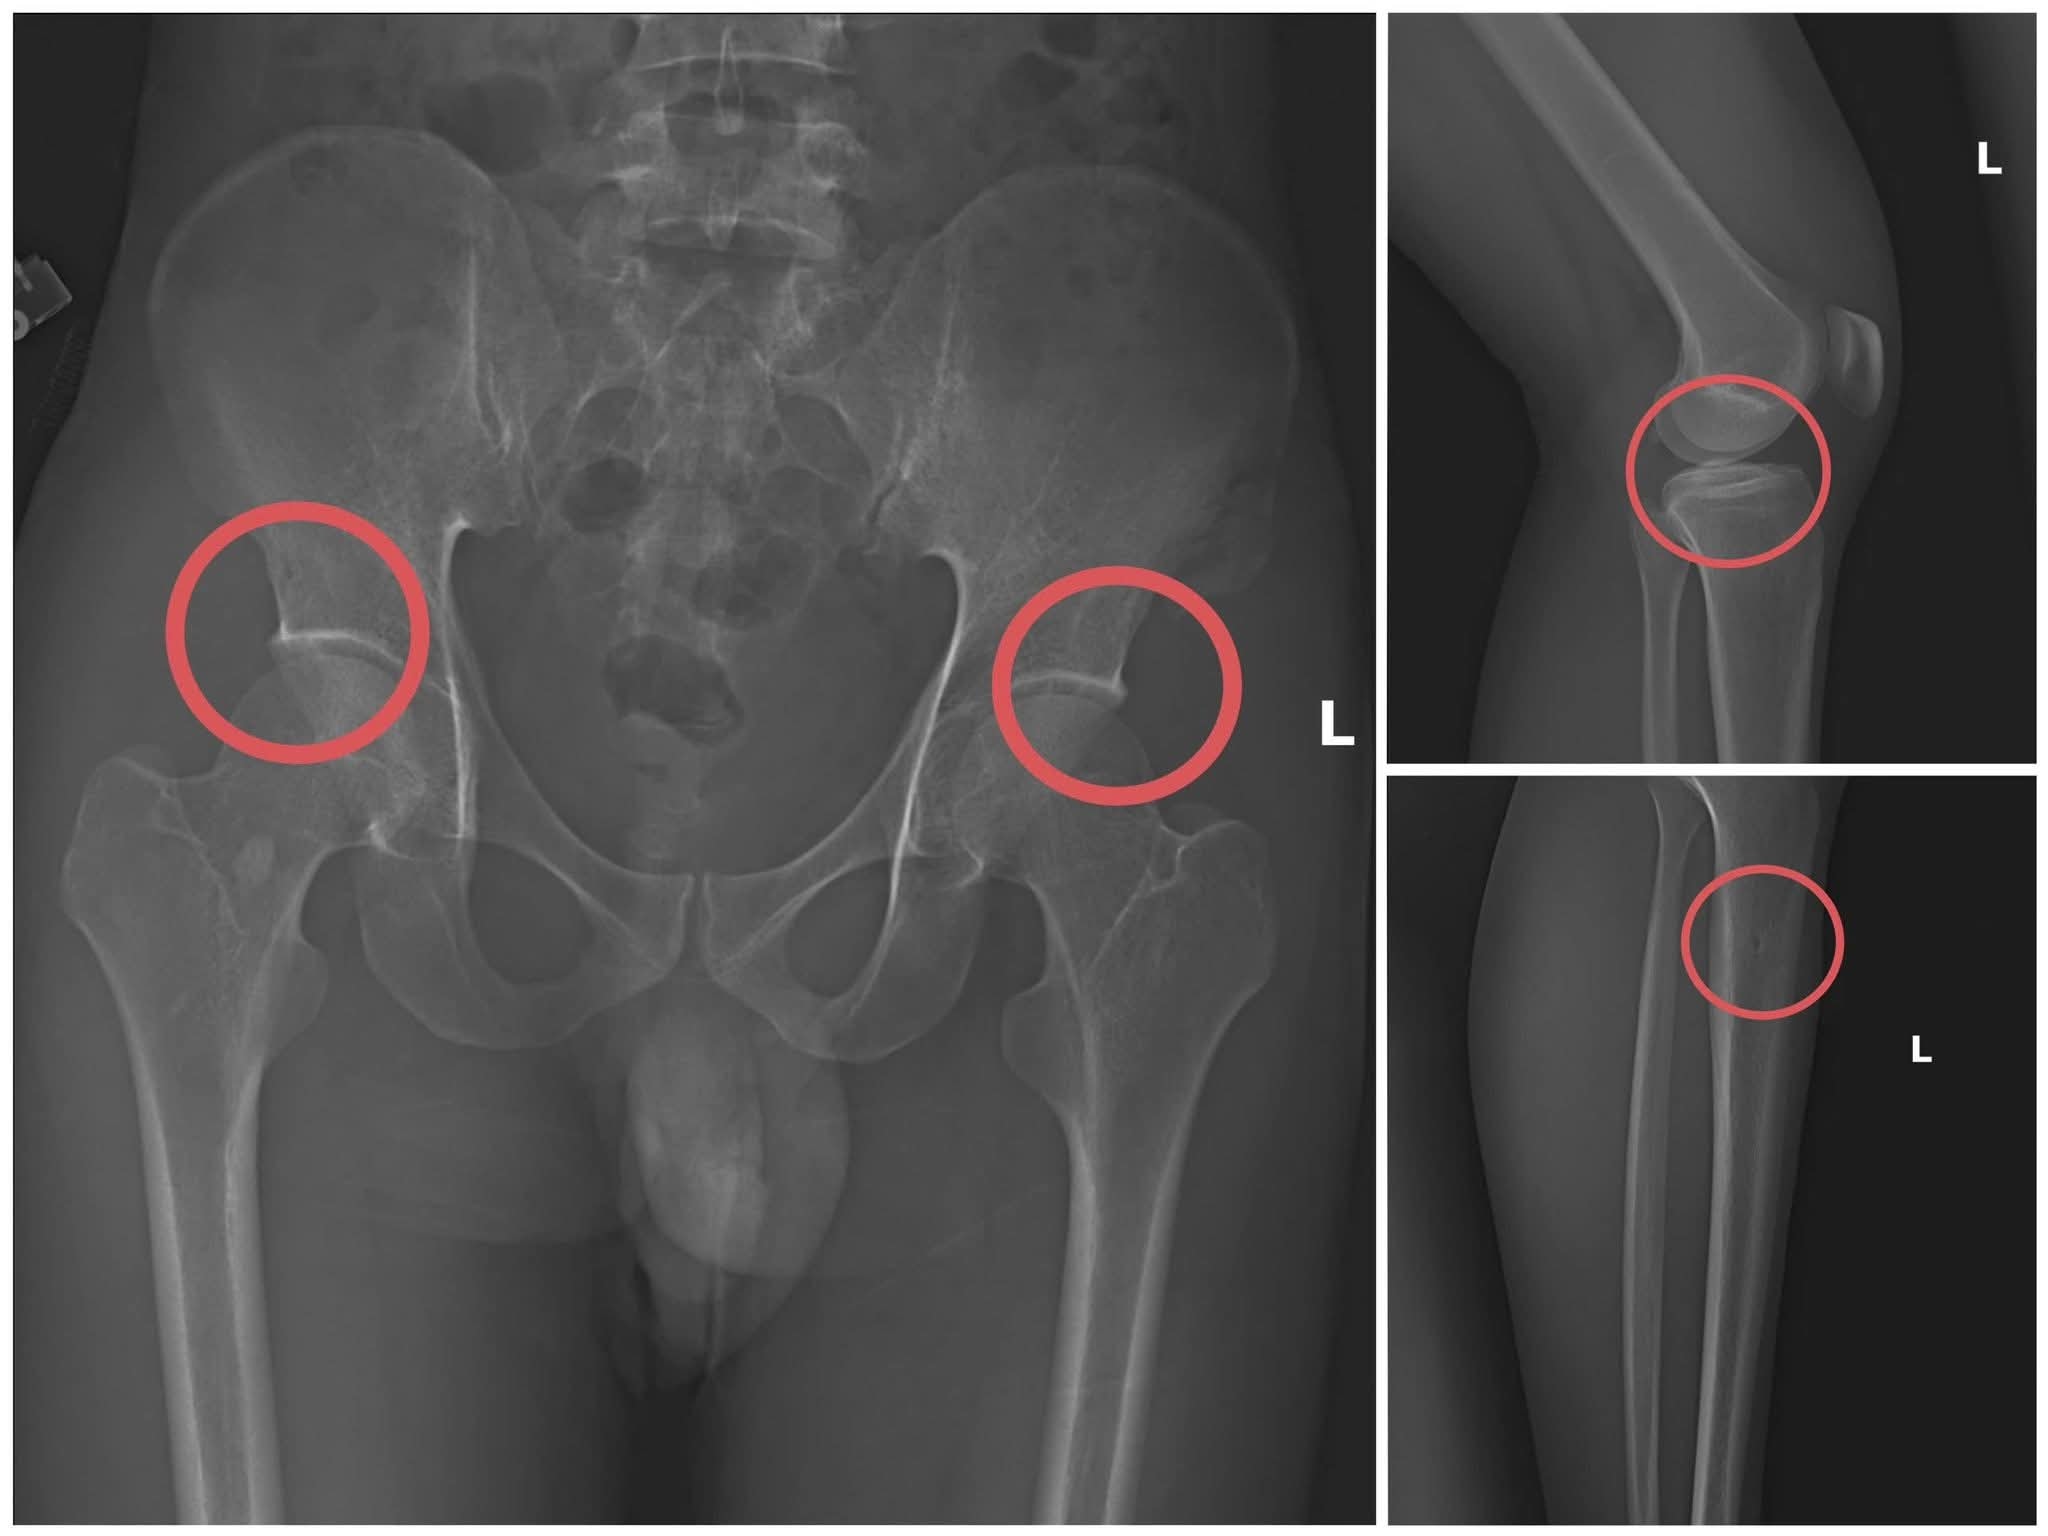

fb_img_1763124608443.jpg

Bản phim chụp XQ xương bị tổn thương do các đối tượng tự gây ra.

Lợi dụng thời gian dài công tác trong ngành y và am hiểu sâu cấu tạo xương – khớp, cũng như cơ chế chi trả bảo hiểm đối với các thương tích gãy xương giá trị cao, Châu đã dựng lên một quy trình trục lợi bài bản, từ việc vận động mua bảo hiểm, tổ chức gây thương tích, đến hợp thức hóa hồ sơ bệnh án để chiếm đoạt tiền của các công ty bảo hiểm.

Đáng chú ý, Châu trực tiếp thực hiện hành vi tiêm thuốc mê, rồi dùng kim tiêm, búa, đinh để tác động vào xương người mua bảo hiểm, tạo nên các vết nứt, vỡ xương tương tự tai nạn thật.

Theo đánh giá của Giám đốc Công an tỉnh Phú Thọ, thủ đoạn này vừa tàn nhẫn, vô nhân tính, coi thường sức khỏe, tính mạng của người tham gia, vừa được tính toán kỹ để gây thương tích đúng vị trí có mức chi trả cao, khiến các công ty bảo hiểm khó phát hiện dấu hiệu gian dối.